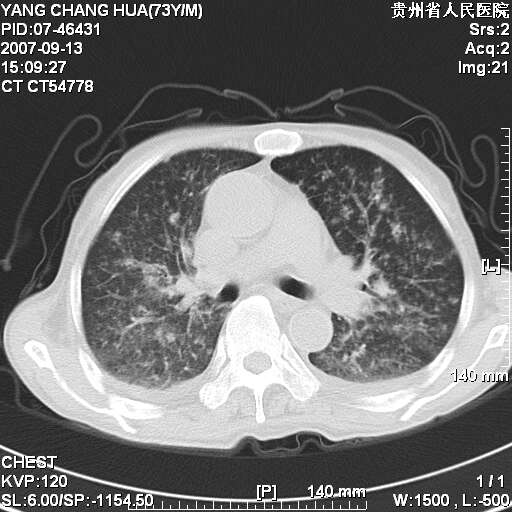

图像没有传全。肺部为感染性病灶;肺囊肿;双侧胸腔积液;肝脾肿大;腹水。

双肺部为感染性病灶.双侧胸腔积液;肝脾肿大;腹水.

双肺部为感染性病灶.双侧胸腔积液;肝脾肿大;脾脏密度不均,不除外脾侵润?腹水.

双肺部为感染性病灶.双侧胸腔积液;肝脾肿大;腹水

图片不全.就这几张图片.无法诊断淋巴瘤的,我考虑:双肺部为炎性病灶.双侧胸腔积液;肝脾肿大;腹水

双肺点片状影,以双上肺改变明显.双侧胸腔积液.为感染性病灶,但不除外结核.

双上肺继发型肺结核。

双侧胸腔积液。

肺大泡。

双肺散在斑片状及多发小结节状阴影,边缘模糊,双上肺野明显,双侧胸膜腔少量积液,纵隔及肺门区未见明显肿大淋巴结,肝脾肿大,脾内见多发低密度区,结合临床考虑恶性淋巴瘤(肺内表现为肺炎肺泡型),单看影像表现,肺结核不能排除。建议结合实验室检查或表浅淋巴结活检。